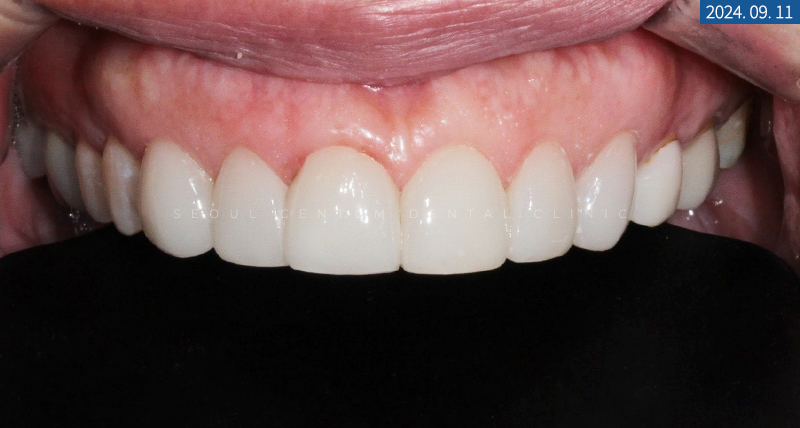

전체 과정을 마무리하고

어느 정도 경화 시간을 가진 후

After 구내 사진을 촬영해서

라미네이트전후 모습을 대조해 보았는데요.

웃을 때 치아가 깨끗해 보이면서

전체적으로 단정한 모습이 됐습니다~

전의 누렇고 마모된 부분이 전부 개선되는

무삭제라미네이트 특성상

새로운 치아로 재탄생된 것이랍니다.

환자분께서는 단정하고 깔끔함을 원하셨기에

그 방향으로 디자인해 드렸는데,

미세하게 시크함과 연예인 느낌,

사랑스러운 느낌까지 들게끔

만들어드릴 수 있었습니다.